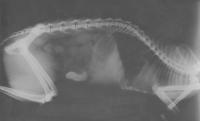

Krank

Ursache war ein Ballen aus Haaren und Gras, der sich im Laufe der Zeit in ihrem Darm gebildet hat und zu einem schleichendem Darmverschluß führte.

Röntgenbilder:

Röntgen1 Röntgen2

Die Operation am 1. September hatte sie gut überstanden. Ihr Körper war aber zu geschwächt um sich wieder zu erholen.

Susi starb am 4. September 2000 um 13.30 Uhr auf Grund ihres schlechten Allgemeinzustandes, Herzschwäche, Leberentzündung und Blutarmut. Sie wurde leider nur 7 Jahre und 5 Monate alt.